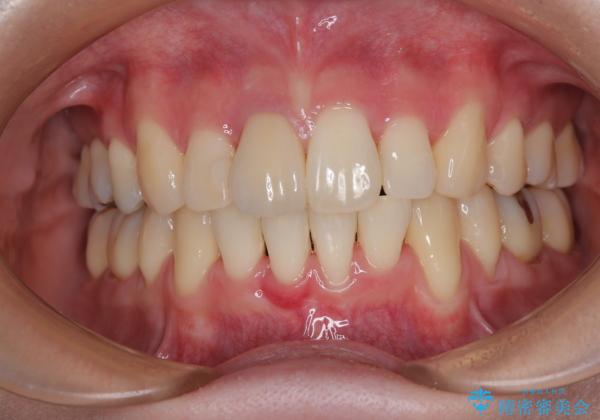

- 八重歯と上の前歯が出っ歯になっていることを気にして来院された患者様です。

横から見た際の口元の飛び出した印象も改善したいとのことで、上下左右の第一小臼歯4本を抜歯し、ワイヤー装置にて抜歯矯正を行うこととしました。

前歯の変色している歯は、神経組織が壊死していたため、矯正治療前に根管治療を実施し、矯正治療後にオールセラミッククラウンにて補綴治療を行うこととしました。

順調に歯が動き、補綴治療も含め2年弱で治療を終えることができました。